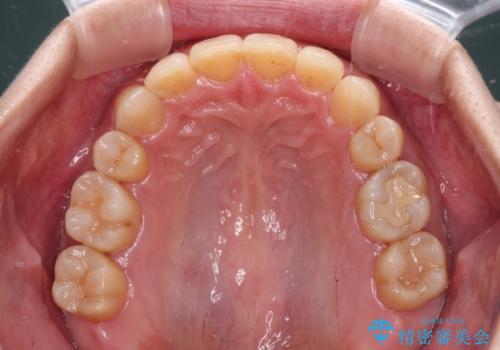

下顎2前歯の欠損 インビザラインによる抜歯矯正

- 下顎前歯欠損による歯列不正を気にして来院された患者様です。

下顎の歯列が小さく、下顎前歯が隠れてしまう過蓋咬合(ディープバイト)であったため、

マウスピースでの抜歯矯正特有の抜歯スペースに向かって奥歯が傾斜する動きが顕著に表れ、ディープバイトは改善されませんでした。

前歯のみが強く接触し、奥歯で咬めない期間も続いたため、ワイヤー装置などを補助的に使用し、何とか終了させることができました。